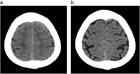

1. 頭部画像所見では、脳室拡大所見とともに

1. 不均衡に拡⼤したクモ膜下腔(脳溝)所見であるDESH(Disproportionately Enlarged Subarachnoid Space)所見

1. 拡大したシルビウス裂所見、高位円蓋部脳溝の狭小化所見、急峻な脳梁角所見などに注目する。

1. 画像診断上、DESH所見、脳梁角の急峻化所見が、iNPHの診断、手術効果予測に有用である。